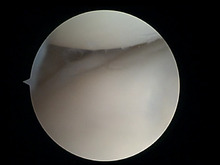

Lateral meniscus damaged tibial cartilage.jpg

Lateral meniscus located between thigh bone (femur, above) and shin bone (tibia, below). The tibial cartilage displays a fissure (tip of teaser instrument).